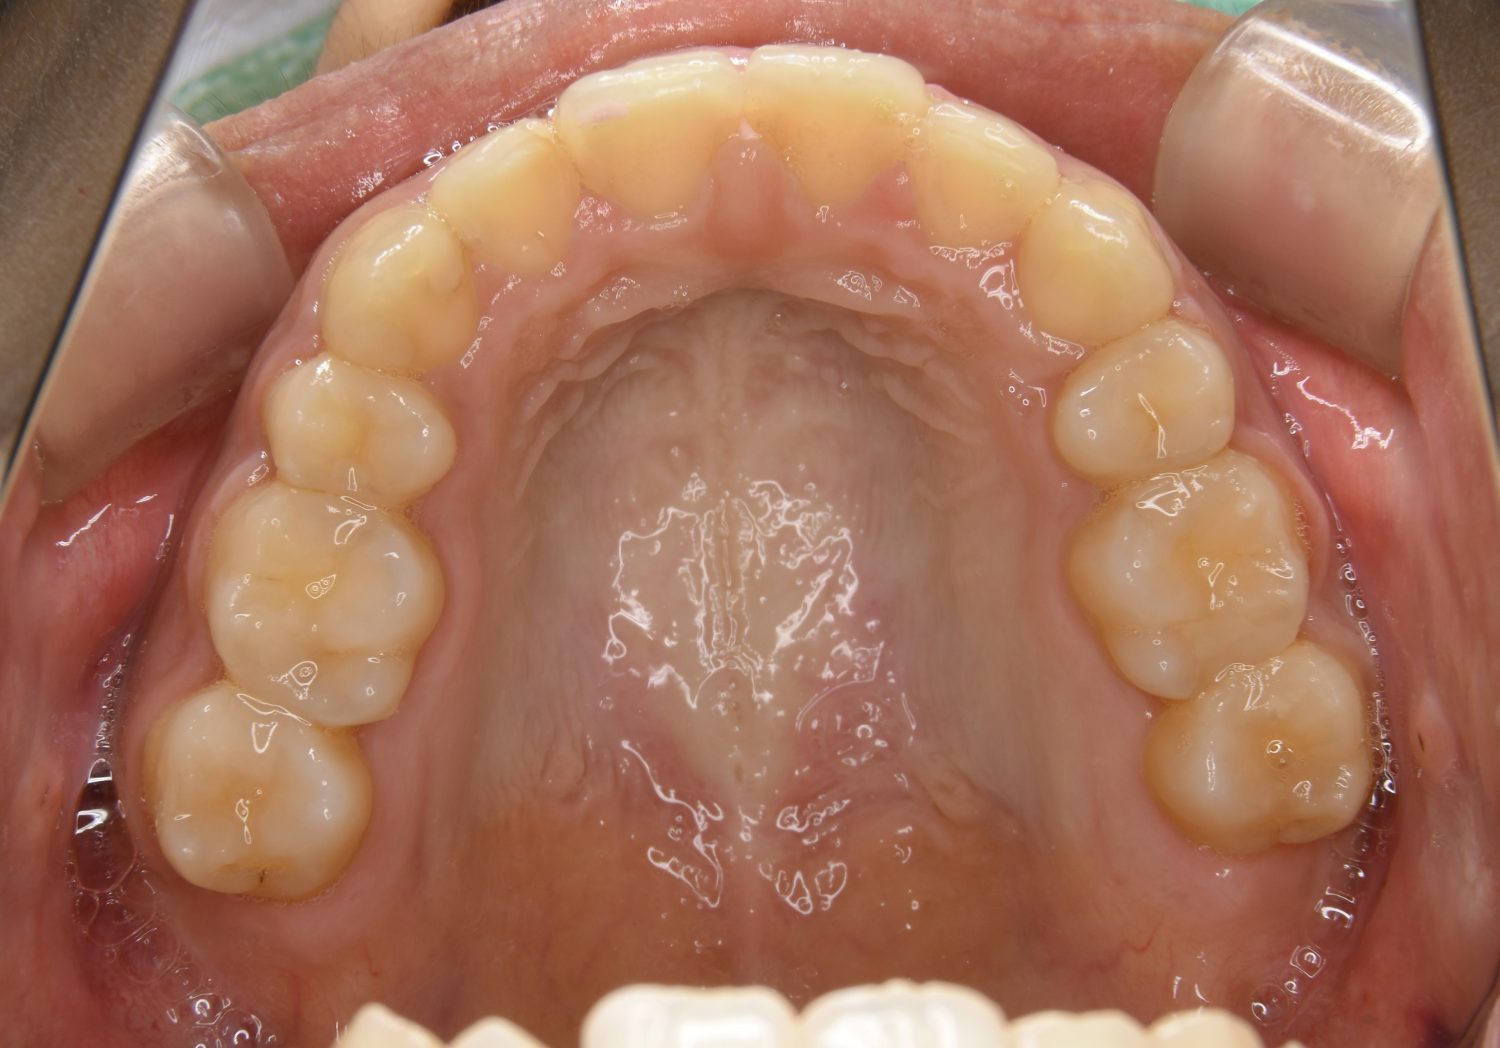

上顎前突の症例紹介①

Before

After

主訴

上の歯が出ている。歯並び全体が気になる。

治療内容

上顎両側第一小臼歯を抜歯し、上下ラビアルブラケット(唇側装置)に矯正用アンカースクリューを併用し治療を行いました。

治療費

1,000,000 円(税込)

治療期間

26ヶ月

通院回数

25回

想定されたリスク

※なし

丸山和宏先生

ピーススマイル矯正歯科

上顎前歯の前突により口元の突出が認められました。上の左右の第一小臼歯を抜歯し上顎前歯を後退させることで口元の突出感は改善し、咬合も良好な状態となりました。